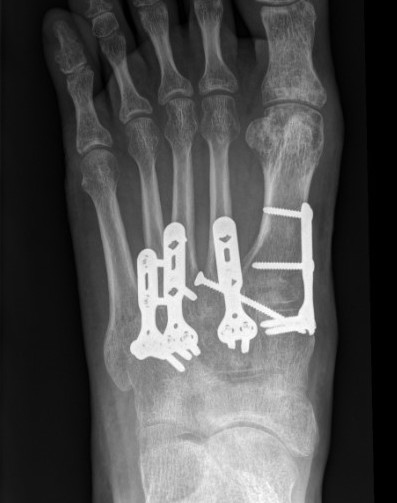

Bridge plating of 1st, 2nd, 3rd & 4th TMT with screw fixation of Lisfranc joint